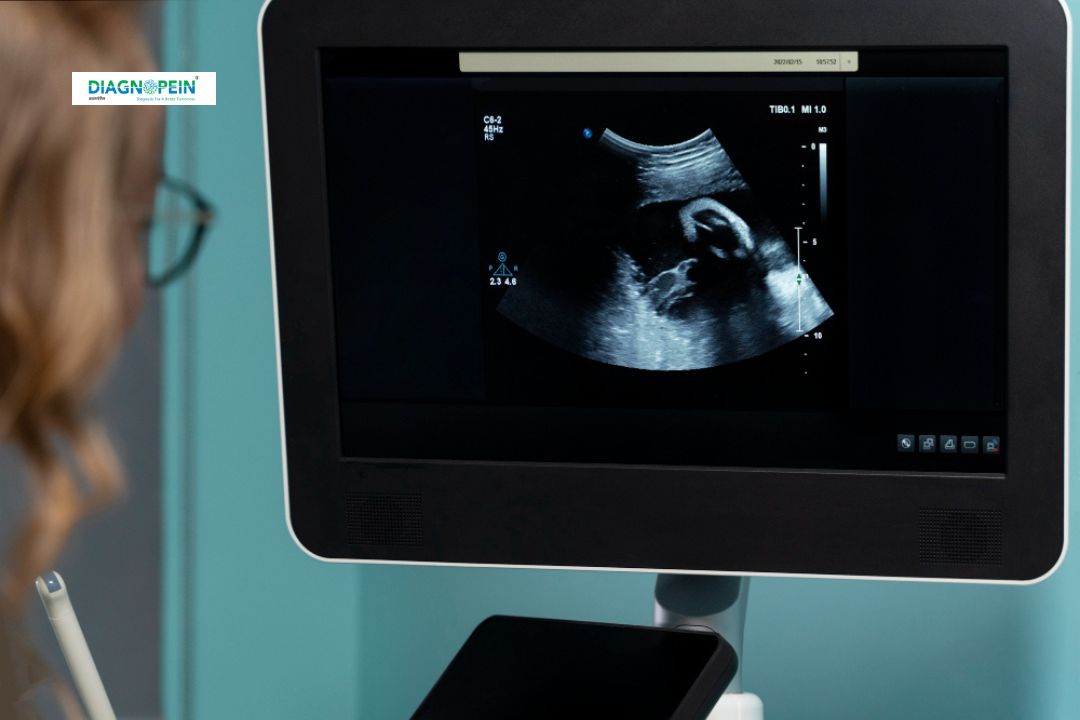

USG Growth Scan is a specialized ultrasound test used to monitor the growth and well-being of a baby during pregnancy. Typically performed between 28 to 38 weeks of gestation, this scan evaluates fetal size, weight, and development by assessing important parameters like amniotic fluid, placenta position, and blood flow. The USG Growth Scan in Karad helps confirm whether the baby is growing at a normal rate and ensures both mother and child remain healthy throughout pregnancy.

The USG Growth Scan procedure is simple, comfortable, and typically takes about 20 to 30 minutes. You will be asked to lie down on an examination bed. A water-based gel is applied to the abdomen to help the ultrasound transducer glide smoothly. The sonographer then moves the probe over the belly to capture detailed images of the fetus.

During the Ultrasound Growth Scan, the sonographer measures fetal body parts such as the head (BPD), femur length (FL), abdominal circumference (AC), and head circumference (HC). These measurements are used to calculate fetal weight, amniotic fluid index (AFI), and growth percentile.